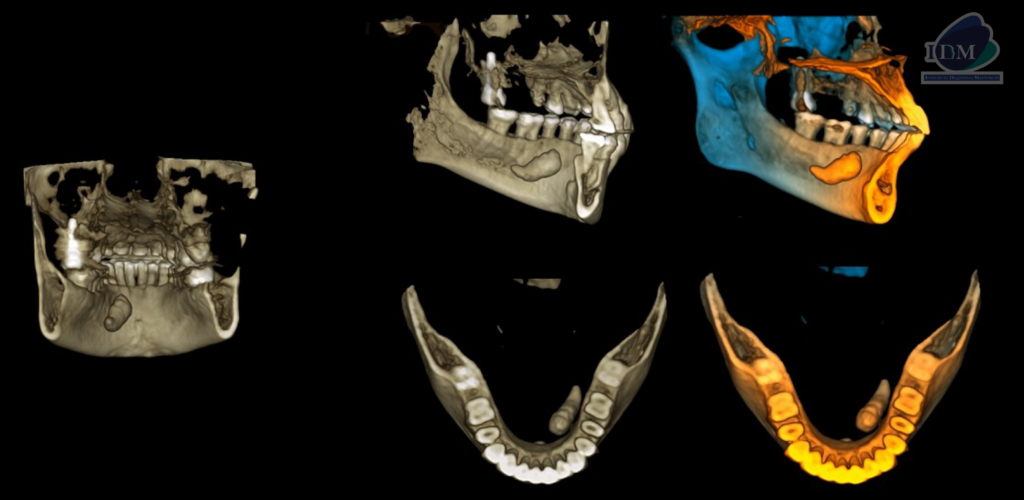

A la evaluación de la tomografía computarizada cone beam en cortes axiales, coronales y transaxiales se observa una imagen hiperdensa con una pequeña área hipodensa central que se localiza por lingual de aproximadamente 20 mm, a nivel del tercio apical de la pieza 33 hasta la raíz distal de la pieza 36. En la reconstrucción en 3D se puede observar de manera más didáctica la relación con las estructuras adyacentes y la forma que presenta, signos imagenológicos compatible con sialolito submandibular.

RECONSTRUCCIÓN 3D